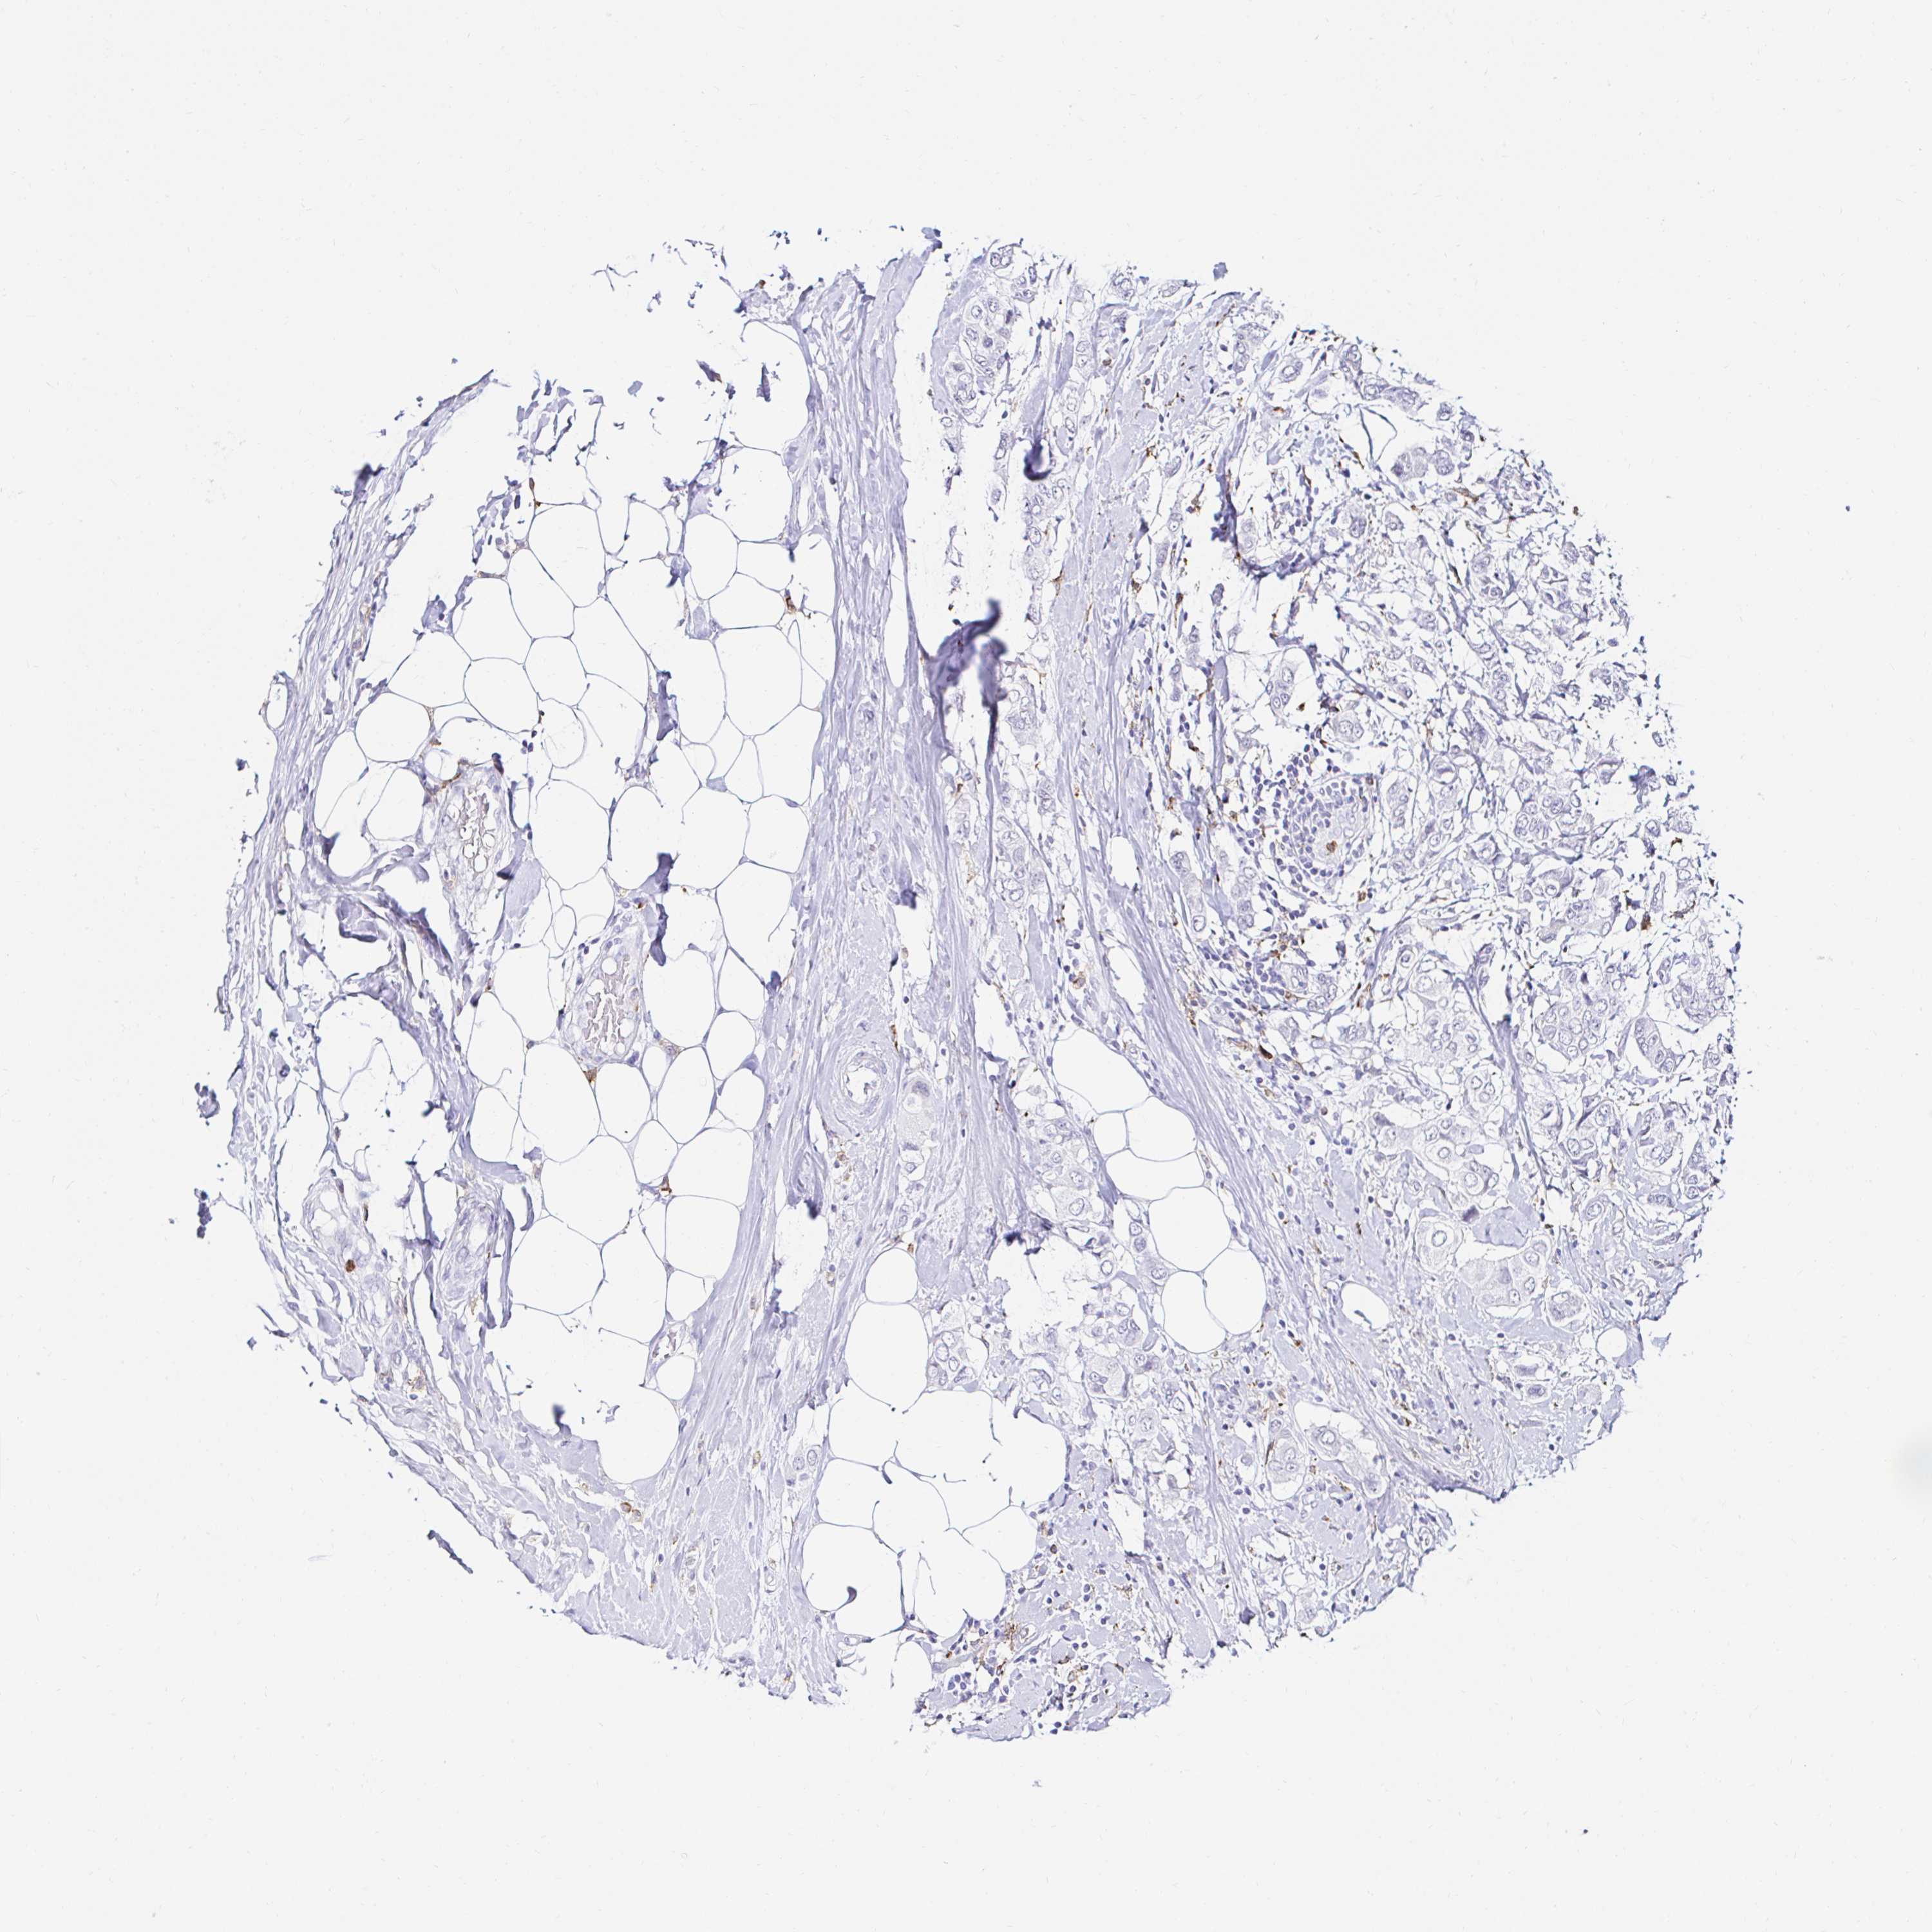

CANCER BREAST CANCER Show tissue menu

BRCA TCGA BRCA VALIDATION PROTEIN EXPRESSION